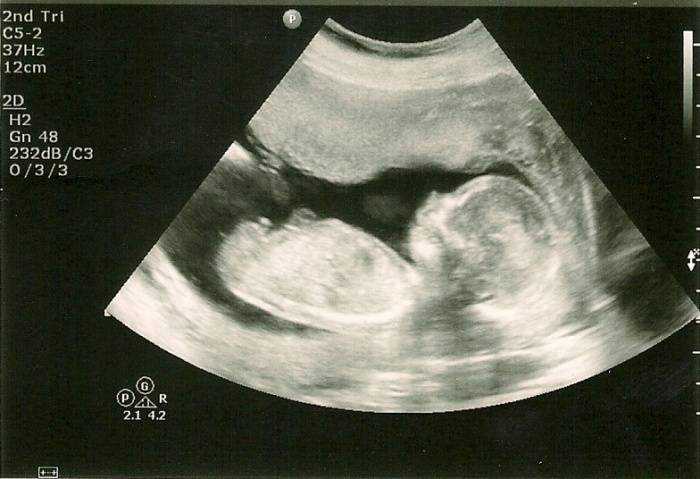

Если УЗИ проводится на 29 неделе беременности, четко видна половая принадлежность малыша. У мальчиков на этом сроке продолжается опускание яичек в мошонку. У девочек клитор немного выдается, так как он еще не прикрыт малыми половыми губами.

В период развития беременности 29 недель наступает время, когда у малыша можно услышать биение сердечка. Также можно тщательно рассмотреть и прослушать работу внутренних органов ребенка, на этом сроке он уже достаточно крупный для этого. Вес малыша на двадцать девятой неделе беременности должен составлять не менее 1200 граммов, а длина тела может превышать 35 сантиметров.

Щечки постепенно округляются вместе с другими частями тела. Так как половые органы сформировались достаточно хорошо, на УЗИ можно уже безошибочно определить пол малыша. С каждым днем организм ребенка начинает функционировать все лучше, превращаясь в гармоничную отлаженную систему. Связки и мышцы продолжают совершенствоваться и крепчать, что ощущается по силе толчков. Учитывая то, что места для кувырканий становится намного меньше, каждый переворот с головы на ноги и наоборот будет четко ощущаться мамочкой.